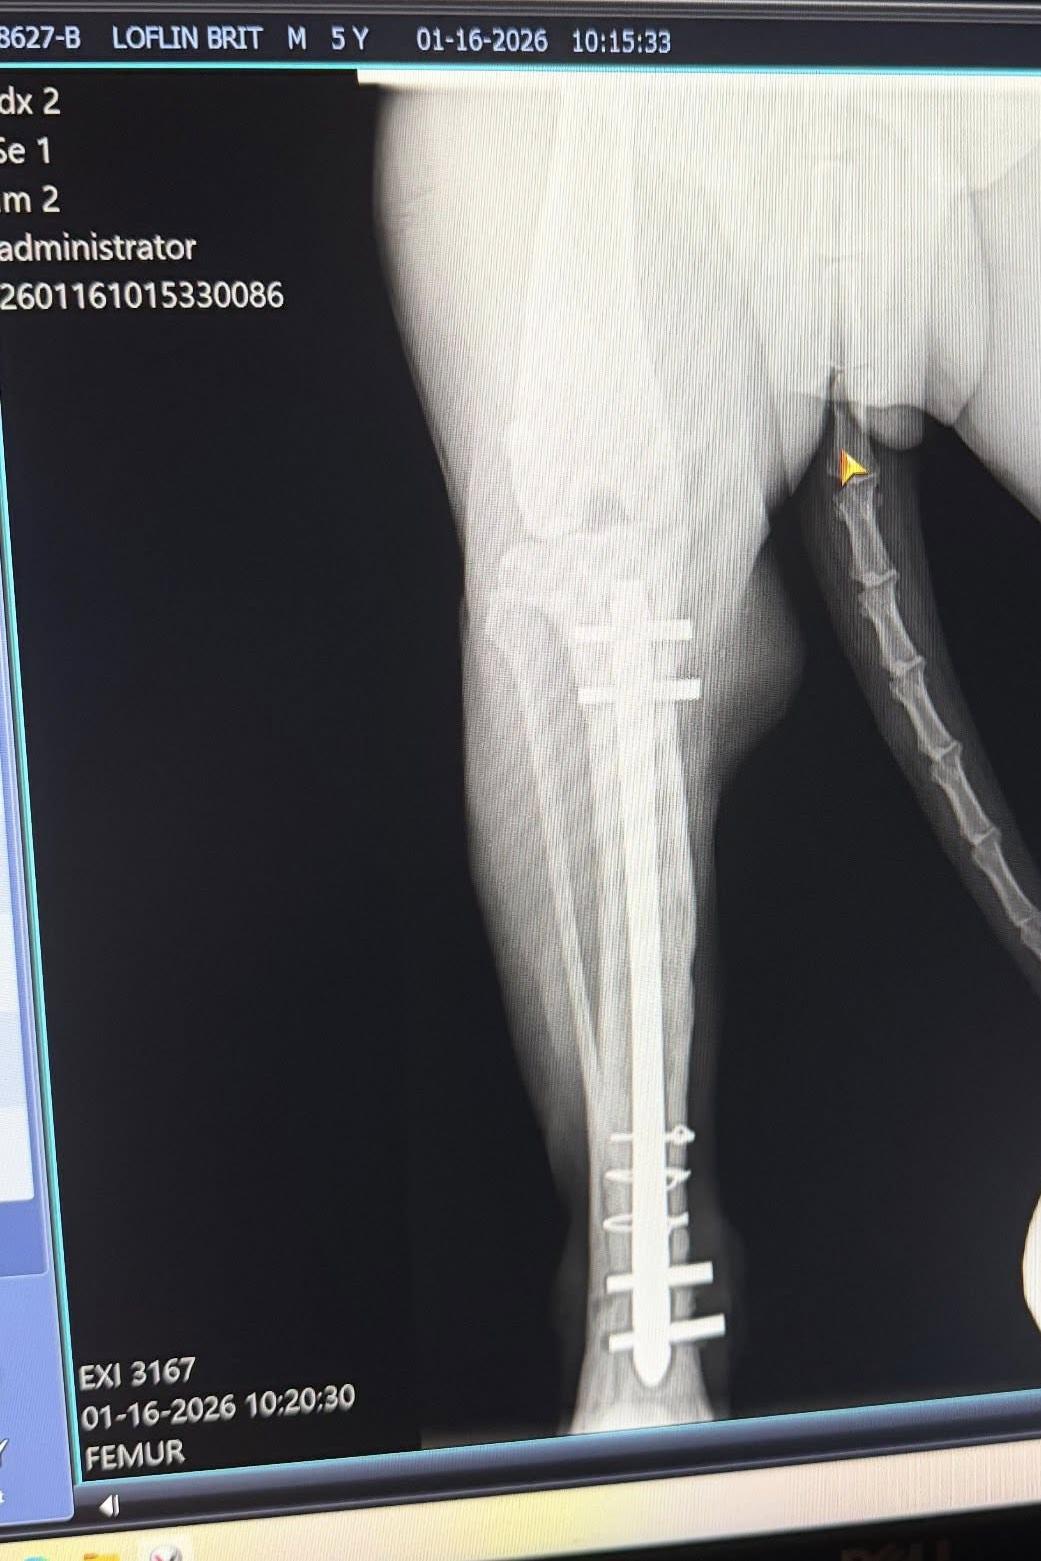

K-9 Brit is a 5 1/2 year old male Belgian Malinois/German Shepherd mix, who honorably served with the Chesterfield County Sheriff’s Office for four years before he was severely injured while still on active duty. K-9 Brit was fetching his reward toy from his Handler, and when he leaped in the air to grab it, he landed awkwardly on his right rear leg, causing a compound fracture. A rod was required to be placed inside of Brit’s leg, along with four screws to hold it in place.

The hardware in Brit’s leg was doing well until recently, when several abscesses were located where the screw placement is. It was determined that the area is currently infected, and that the old hardware needs to be removed, the area of the infection be treated, and replaced with new hardware. This is an immediate medical need for Brit, and surgery has already been scheduled for February 18th, 2026 with an estimated cost of the procedure being up to $3,500.